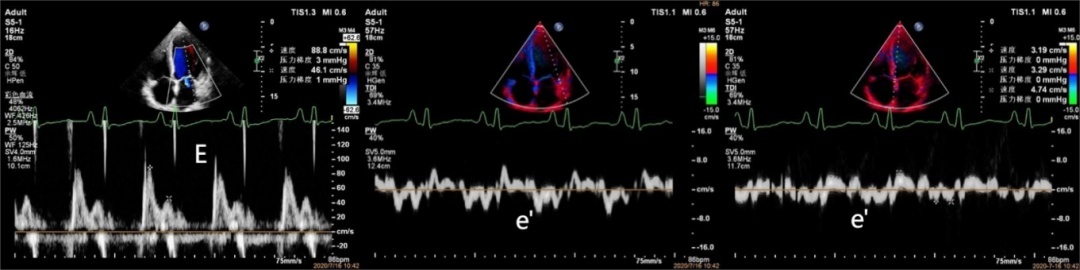

超声报告上,常规可以通过左心室射血分数(LVEF)来判断左室收缩功能,通过左室纵向应变(GLS)早期识别左室收缩功能的异常。二尖瓣舒张期E/A峰比值、二尖瓣组织多普勒间壁及侧壁e’、左心房最大容积指数、三尖瓣反流最大速度等指标进行综合评估左室舒张功能。指南建议使用E/e'识别心脏靶器官损害。

图2:心尖四腔心切面测得二尖瓣口舒张早期峰值流速E,二尖瓣环处室间隔及侧壁舒张早期最大速度e’,获得二尖瓣血流E峰速度与平均e'之比,即 E/e'